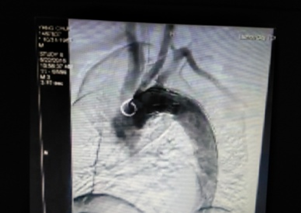

术前CT检查(显示为主动脉夹层)